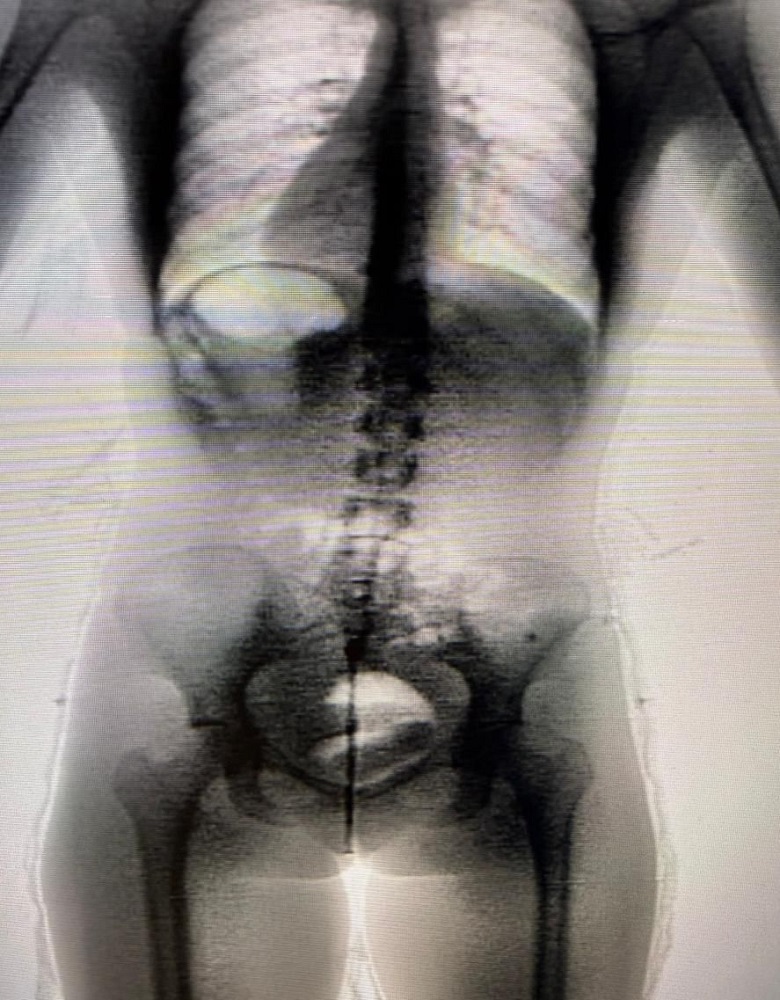

A ocorrência foi detectada por meio do equipamento Body Scan, utilizado no controle de acesso durante o horário de visitação. Por volta das 11h, durante inspeção na Galeria A, o equipamento apontou anormalidade, indicando indícios de possível ocultação interna de material ilícito.

Diante da fundada suspeita, a visitante foi encaminhada ao Hospital Regional de Irecê para realização de exame de imagem complementar (tomografia computadorizada), que confirmou a presença de corpo estranho em cavidade corporal.